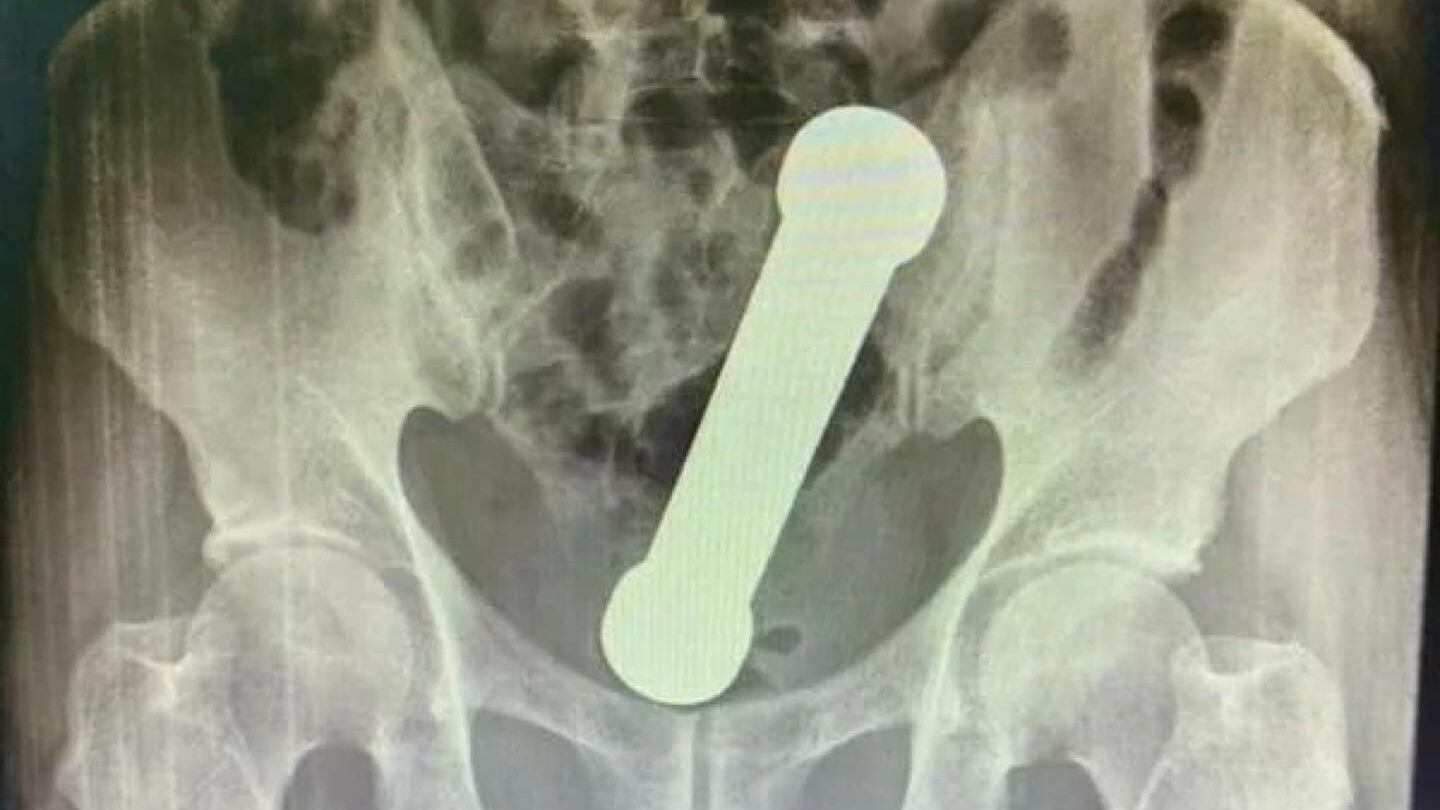

Quando um exame de raio-X foi realizado para a descoberta do problema, foi encontrado um peso de dois quilos dentro do homem.

O objetivo possuía cerca de 20 centímetros de comprimento, da mesma forma dos que são utilizados nas academias de ginástica em exercícios para o braço.

O objeto dentro do homem – um haltere – se encontrava entre o reto e o intestino grosso do paciente. Após o exame, o homem assumiu que teria introduzido o peso de academia no corpo com o objetivo de sentir satisfação sexual.